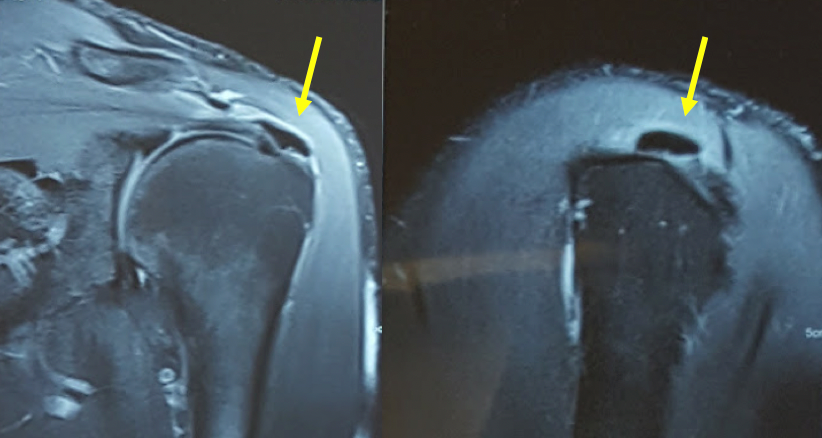

Diagnóstico: pode ser confirmado com o RX, ultra-sonografia ou ressonância magnética.